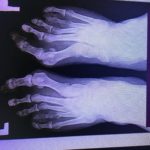

Dość powtarzalną, jest niedorozwój IV kości śródstopia. Powoduje to znaczące skrócenie IV palca. Trudne leczenie nigdy nie kończy się idealnym efektem.

RTG przed zabiegiem